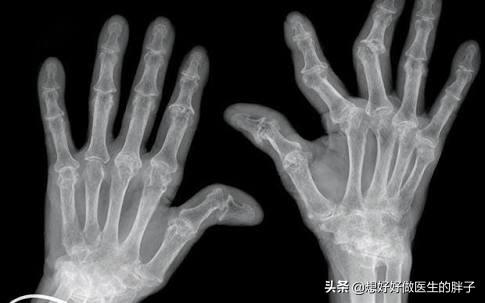

但是如果您看看刺绣一辈子女工五指的时候,当您看到一些常年过度使用膝关节的运动员关节内受损的情况以后,您可能就会对这个理论有一些其他的看法,比如我们国家的著名运动员郎平,据我所知她的周身关节已经手术不下十余次了。